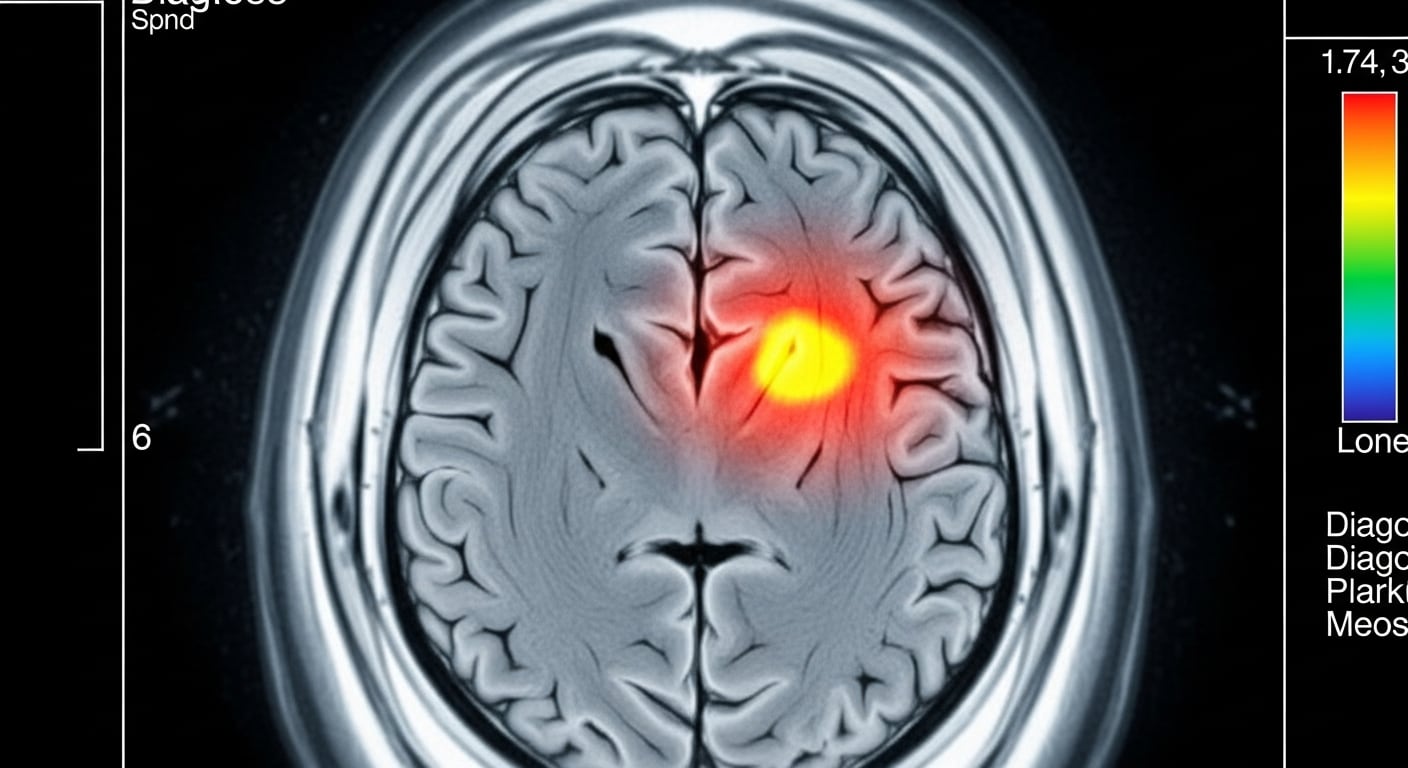

El equipo liderado por el doctor Matthew Campbell, catedrático de genética neurovascular del Trinity College, y el doctor Colin Doherty, director de la Facultad de Medicina del mismo centro, planteó un enfoque innovador: utilizar resonancias magnéticas avanzadas en vida para analizar la permeabilidad de la barrera hematoencefálica en 47 atletas retirados de deportes de contacto, comparando los resultados con un grupo control de personas no atletas y de deportistas de disciplinas sin contacto.

Las tomografías revelaron que la barrera hematoencefálica de los exjugadores de rugby y boxeo era significativamente más permeable que la del grupo de control, incluso después de un promedio de 12 años de retiro. Los participantes con mayor grado de daño en la barrera hematoencefálica tuvieron peores resultados en pruebas de memoria y función ejecutiva.

Campbell precisó: “Esta fue la primera evidencia en el cerebro humano vivo de que la barrera hematoencefálica se ve alterada en individuos propensos a padecer encefalopatía traumática crónica (CTE)”.

Chris Greene, primer autor del artículo y profesor en la Universidad de Medicina y Ciencias de la Salud RCSI, destacó: “El estudio destaca que las resonancias magnéticas centradas en la barrera hematoencefálica podrían servir como un sistema de alerta temprana, identificando a los atletas con mayor riesgo de padecer enfermedades cerebrales en el futuro mientras aún viven y [potencialmente] juegan”.